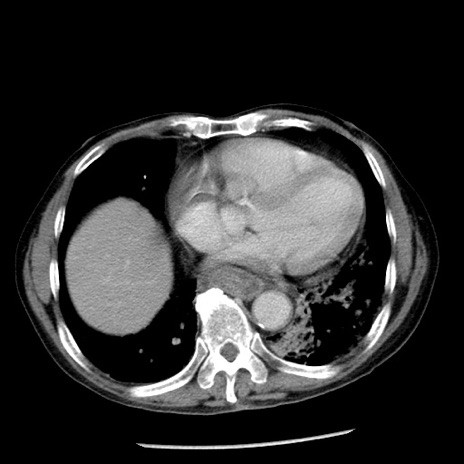

症例26(横断像)

【症例】80歳代男性

【主訴】嘔吐

【現病歴】昨晩2回嘔吐あり、今朝になっても嘔吐あり。来院。

【既往歴】胃潰瘍

【身体所見】意識清明、BT 37.6℃、BP 166/95mmHg、HR 100bpm、SpO2 97%、腹部:平坦・軟、腸蠕動音聴取良好、圧痛なし。

【データ】WBC 21900、CRP 1.46